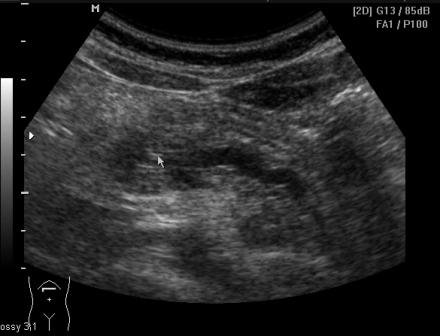

На момент осмотра пациентку ничего не беспокоит. В моче диастаза 3300.

Размеры поджелудочной:16мм -11мм-17мм

Сегодня девочка пришла на плановое УЗИ: